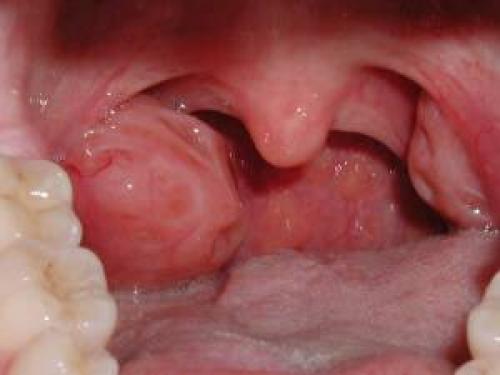

Тонзиллит

Нередко процесс охватывает только одну миндалину (суть патологии кроется в воспалении небных миндалин которых две). Потому так часто встречается неравномерный характер болевых ощущений.

Патология провоцируется стафилококками (золотистыми), зеленящими стрептококками, хламидиями, микоплазмами, уреаплазмами, вирусами герпеса, папилломавирусом.

Симптомы достаточно специфичны. Это односторонние боли в горле жгучего, тянущего характера, усиливаются при глотании, иррадиируют (отдают) в зубы, шею, челюсти. Так же характерна опухлость лимфоузлов на шее, нарушения дыхания по типу одышки или удушья.

Это опасное проявление, вполне способное закончиться отеком тканей глотки и асфиксией.

Также наблюдаются зуд в предверии мягкого нёба, повышение температуры тела, проблемы с общим состоянием. Объективно отмечается покраснение горла, рыхлость его структуры, налет с одной или обеих сторон.

Иное название тонзиллита — ангина.

Лечение классическое, комплексное. С применением противовоспалительных, антибиотиков, иных названных препаратов. Для нормализации иммунитета рекомендуется принимать иммуномодуляторы.